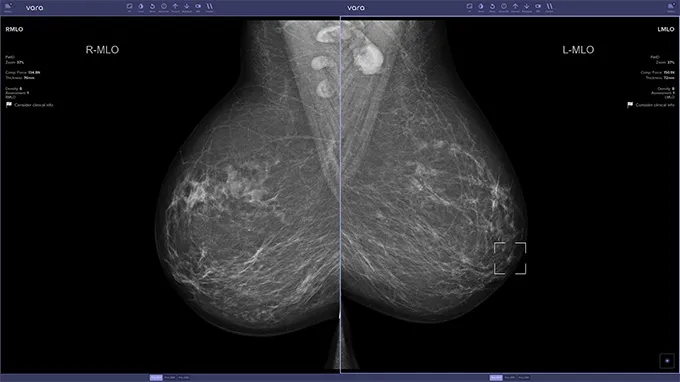

看看人工智能是否可以,在全国 12 个筛选点安装了决策转介软件。 2021 年 7 月至 2023 年 2 月下旬,超过 46 万名 50 至 69 岁的女性参与了这项研究。人工智能将乳房 X 光检查标记为正常、可疑或未分类。 119 名参与的放射科医生选择使用人工智能支持的图像查看器,该查看器显示了软件对大约一半女性筛查的评估结果。

人工智能如何最适合放射科医生的工作流程仍然是一个悬而未决的问题,但它可以取代最初的读者之一,开发人工智能的柏林医疗保健技术公司 Vara 的首席技术官兼联合创始人 Stefan Bunk 表示。 “现在应该开始讨论了。”